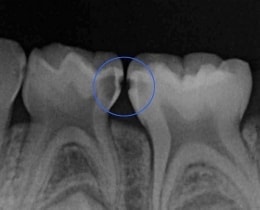

②治療前レントゲン写真

レントゲン写真でみると、歯と歯の間に虫歯がある様子がわかります。